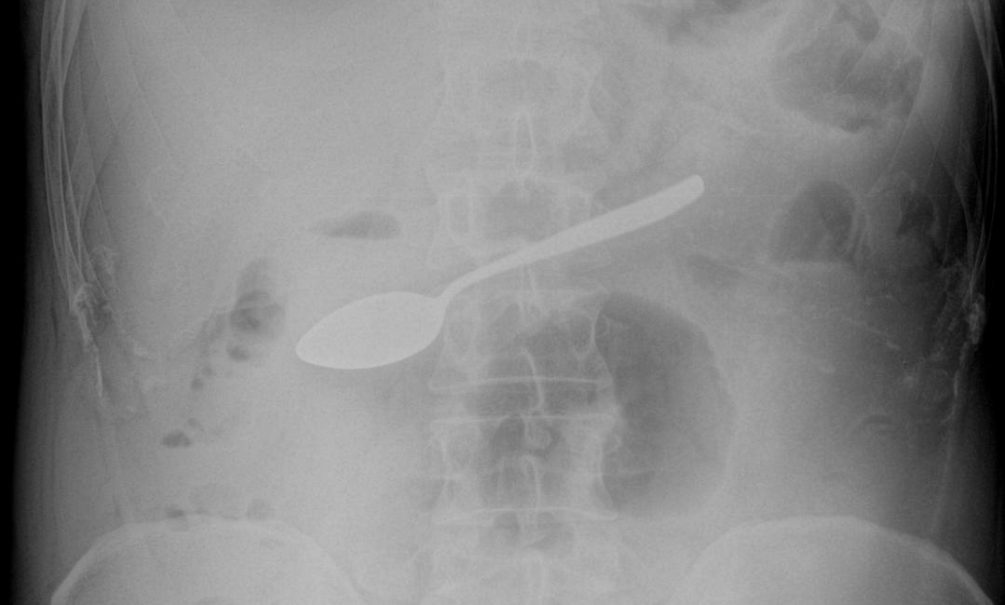

В Мытищинскую больницу Московской области поступил 42-летний мужчина, который жаловался на тошноту, рвоту и повышенное слюноотделение. Медики провели диагностику и нашли в его желудке десертную ложку. Об этом рассказали в пресс-службе министерства здравоохранения Подмосковья.

Врач-эндоскопист Максим Щипачев поделился, что прибор пришлось вытаскивать через пищевод с помощью эндоскопического оборудования, чтобы избежать открытой операции. По словам медика, процедура была непростой, потому что на пути к освобождению ложки было несколько сужений, в том числе переход из пищевода в ротоглотку. Однако всё прошло успешно.

«Если вовремя не извлечь из пищеварительного тракта крупный металлический предмет, то может начаться угрожающее жизни внутреннее кровотечение. Вероятность того, что предмет беспрепятственно выйдет из организма естественным путём, ничтожна», — поделился Щипачев.

На текущий момент мужчина чувствует себя хорошо, его уже выписали и отправили домой лечиться. Он не стал раскрывать истории, как десертная ложка оказалась у него в таком необычном месте.